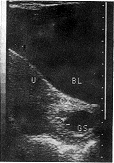

中国超声医学杂志990134 患者女性,28岁。孕2产0。因停经2月余,腹痛伴阴道流血3天,加重1天入院。妇科检查:外阴、阴道血染,宫颈光滑,宫口闭,无触痛,子宫前位、增大如孕2+周大小、质软、轻压痛。临床诊断:难免流产。B超检查:子宫前位,形态正常,宫体增大,为6.6cm×6.5cm×4.8cm,内部回声均质,宫内膜增厚1.6cm,宫颈膨大、内口开放,在宫颈管内探及一孕囊回声,大小为3.1cm×2.1cm,其内未见胚芽回声(附图),B超诊断:宫颈流产。

附图 GS:孕囊;U:子宫;BL:膀胱